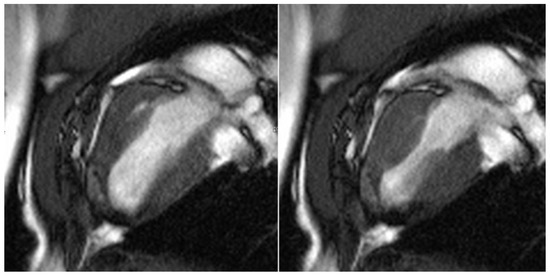

All test animals were examined six months after successful surgery using cardiac MRI to evaluate the morphology and function of the left ventricle, particularly in the area of the transplanted patches of stomach tissue. In line with the macroscopic findings, stable integration of the stomach patch through adjacent cicatricial tissue could be detected in animals without an aneurysm (see Figure 7).

Figure 7.

Cardio MRI six months following myocardial reconstruction with a vascularized stomach patch, stabilized with degradable magnesium alloy scaffolds. Cine SSFP in left ventricular two-chamber view. Left: end-diastolic phase, right: end-systolic phase. Good integration of the transplanted stomach patch.

The border zone between the myocardium and the stomach patch showed an intense late enhancement of the contrast agent as an expression of the adjacent stabilizing fibrotic remodeling processes in these animals (see Figure 8).

Figure 8.

Cardio MRI six months following myocardial reconstruction with a vascularized stomach patch, stabilized with degradable magnesium alloy scaffolds. Delayed enhancement imaging. Left: cine SSFP. Right: four-chamber view with signs of distinct late enhancement in the left ventricular, apical zone, indicating cicatricial remodeling.

However, the left ventricular ejection fraction was still reduced (50%), and the region of the stomach patch was akinetic. There was a paradoxical systolic outward movement of the affected area and a reduction of left ventricular ejection fraction of 15%–18% in the animals with an aneurysm. The aneurysms had a total volume of 12–18 mL. The delayed enhancement of the contrast agent was seen in these animals, mainly in the border zone between the native myocardium and the stomach tissue.